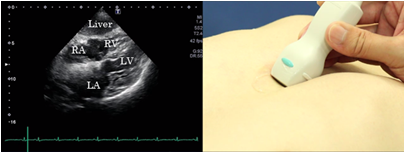

Epigastric 4 chamber view

To obtain the epigastric 4 chamber view, place the probe horizontally under the xiphoid process and press it with the tip directed upward. Fix the image when the 4 chambers look the largest and the atrioventricular valves on both sides are clearly visualized. This view is suitable for observation of atrial septal defects and pericardial effusion. It is also suitable for observation of the presence or absence of signs of pericardial adhesions.